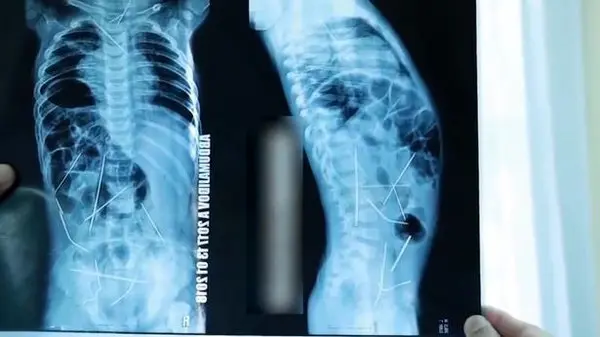

بیرون کشیدن 16 سوزن از بدن کودک 11 ماهه +تصاویر وحشتناک

رکنا: پزشکان ازبکستانی پس از جراحی سنگین و نفسگیر 9 ساعته از بدن کودکی 11 ماهه، 16 سوزن بیرون آوردند که در نقاط مختلف بدنش نفوذ کرده است.

به گفته پزشکان، سوزنها در قلب، گردن، ستون فقرات، روده بزرگ و مثانه کودک فرو رفته بود.

پزشکان برای خارج کردن سوزنها از بدن کودک، 9 ساعت جراحی نفسگیر داشتند.

پروفسور «کابیبولا آکی موو» سرپرست تیم جراحی در این باره گفت: «سهل انگاری مادرکودک سبب شده که فرزندش هنگام بازی و در تنهایی، سوزن ها را ببلعد و برایش دردسر ساز شود. ما با انجام سی تی اسکن بدن کودک متوجه سوزنها شدیم و همه را به سختی از بدنش بیرون آوردیم.»برای ورود به کانال تلگرام ما کلیک کنید.